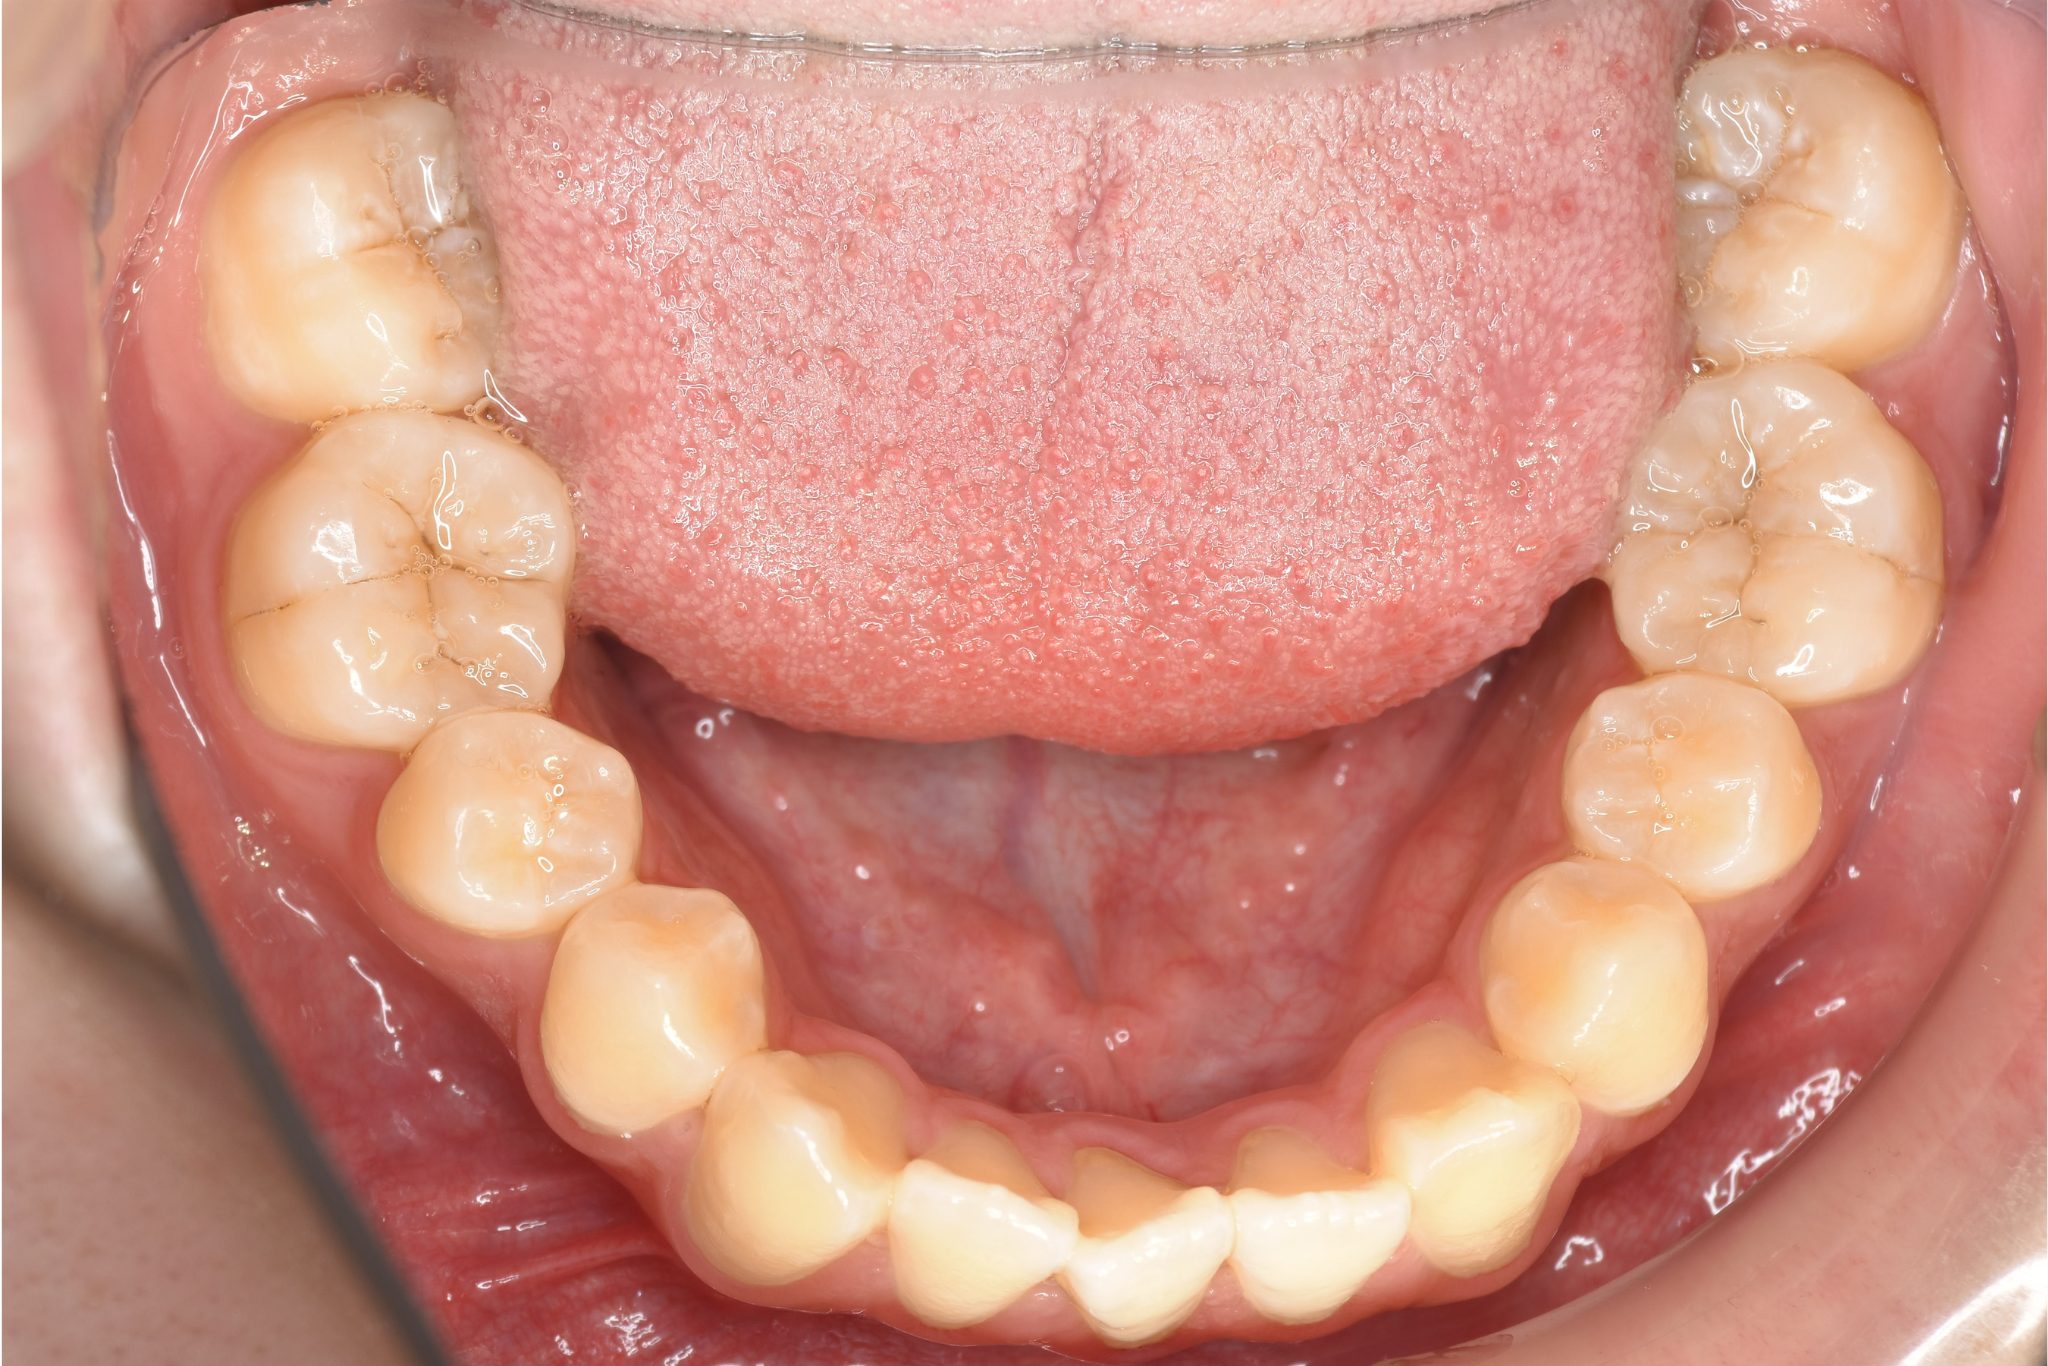

ワイヤー矯正治療|症例_037